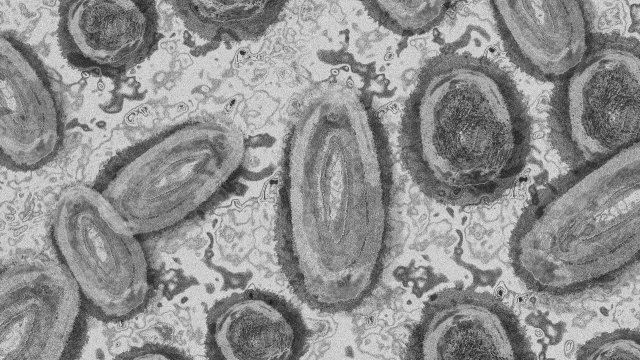

... новият вариант на Ковид-19, известен като „Нимбус“ (NB.1.8.1), се разпространява по-бързо от предишните щамове, но засега няма доказателства, че води до по-тежко протичане на болестта.

Нов вариант на COVID 19 обозначен като NB 1 8 1 буди безпокойство сред

...... доказателства, че той предизвиква по-тежко заболяване в сравнение с други варианти. Симптомите на NB.1.8.1 трябва да са близки до тези на другите подварианти на Omicron.

Нов вариант на COVID 19 обозначен като NB 1 8 1 буди безпокойство сред

...... NB.1.8.1 трябва да са близки до тези на другите подварианти на Omicron. ТЕМА преди 1 месец 1569 преди 4 месеци 970 преди 5 месеци 5116

Съвсем нов и силно заразен вариант на Ковид 19 обозначен като

Нов и силно заразен вариант на COVID 19 обозначен като NB 1 8 1

Нов и силно заразен вариант на COVID 19 обозначен като NB 1 8 1

Нов и силно заразен вариант на COVID 19 обозначен като NB 1 8 1

Новият подвариант на COVID 19 e по заразен но няма данни за